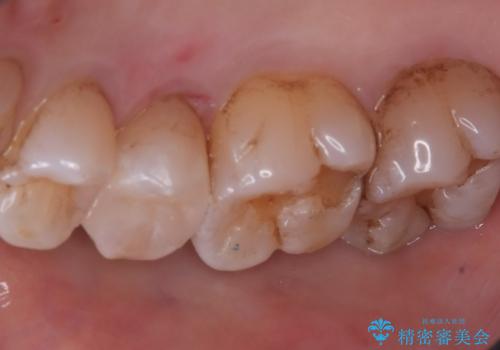

右上5番にう蝕があり、審美性・適合性・材料安定性の高いセラミックインレーでのやり替えとなりました。

右上5番の近遠心にう蝕が認められたため、CR裏層の後MOD窩洞のセラミックインレーとしました。

インレーセット時はラバーダム防湿を行っています。